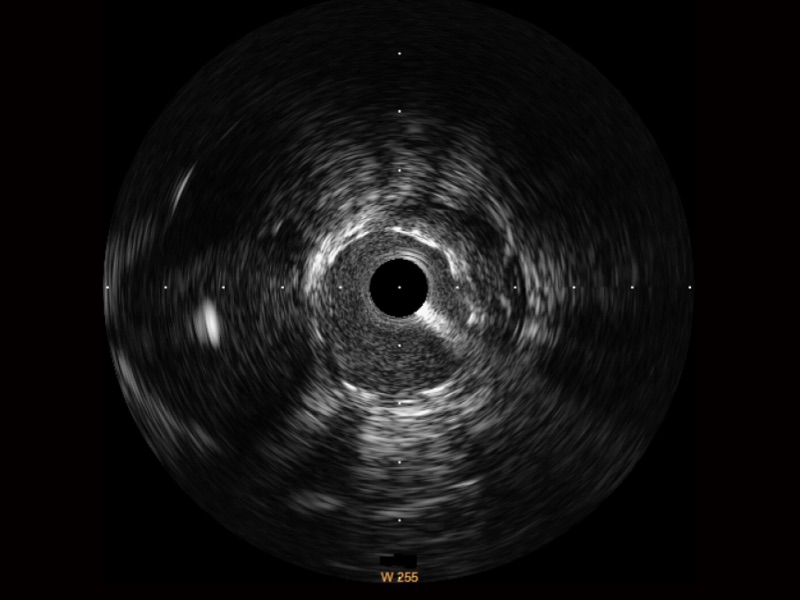

狗万官方网站宽频IVUS图像

对比传统IVUS导管成像,狗万官方网站宽频IVUS图像的近场支架梁显影更细腻,远场中膜外血管仍清晰可辨,兼顾远中近,兼顾分辨力与穿透深度